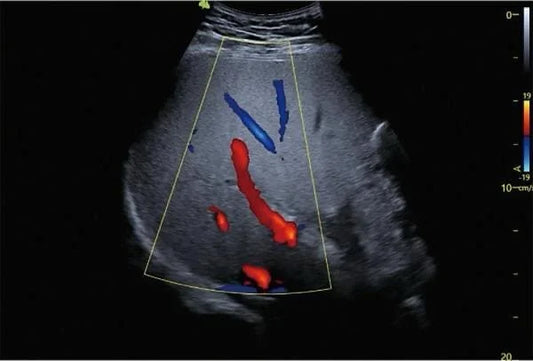

Ecografía obstétrica y diagnóstico fetal avanzado

La historia se repite más de lo que debería. Una IPS mediana en una ciudad intermedia de Colombia decide renovar su sala de ecografía. El volumen de pacientes embarazadas ha...